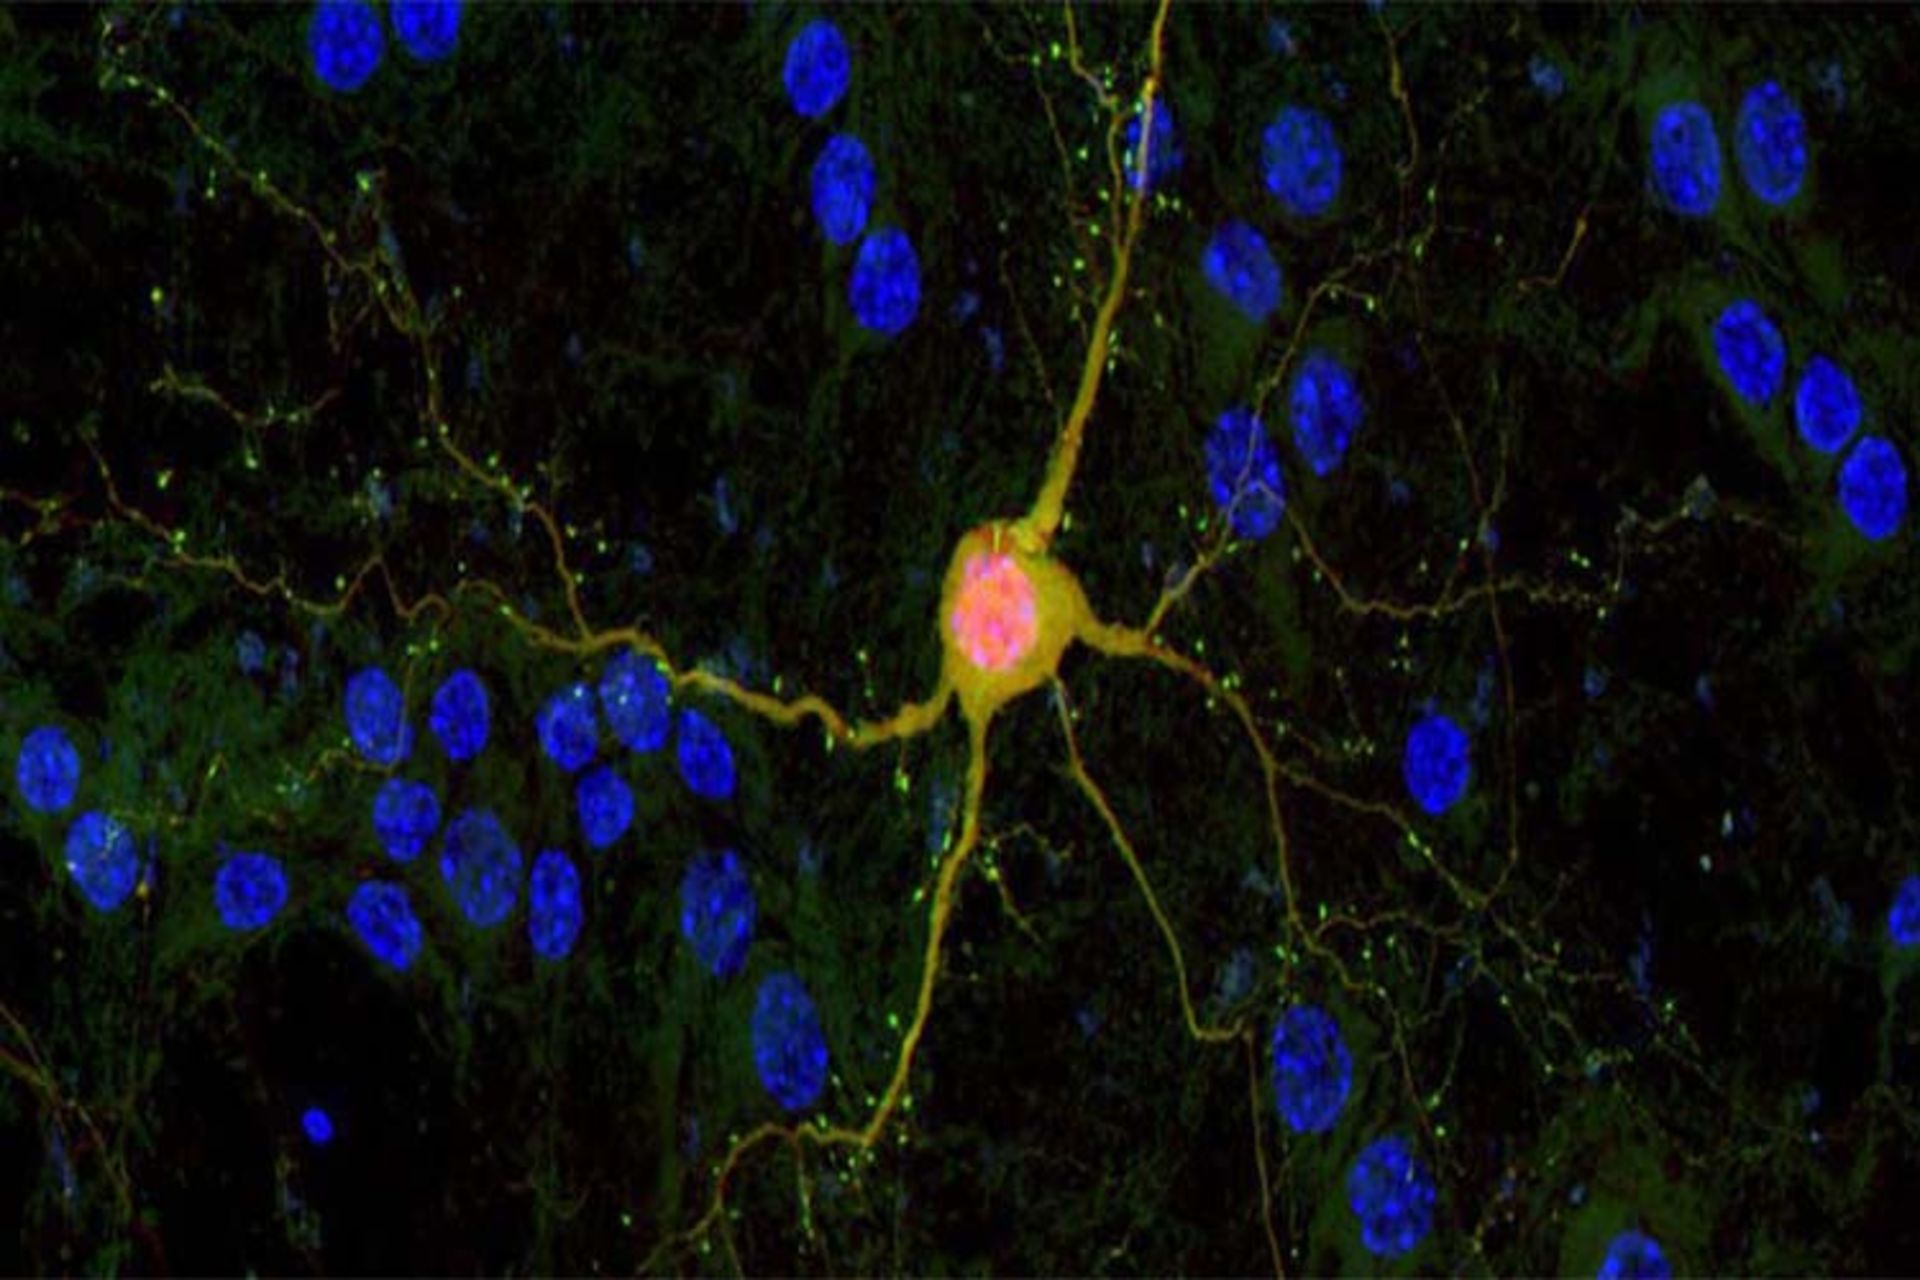

به تازگی دانشمندان روشی را برای کاشت نورون‌های سالم در مغز بیماران عارضه‌ی مغزی ارایه داده‌اند که بر اساس چاچوب‌های سه‌بعدی و تزریق نورون‌ها درونشان ایجاد شده است. این روش در صورت تایید استفاده روی انسان می‌تواند به جایگزین‌سازی عصب‌های آسیب‌ دیده ناشی از بیماری آلزایمر در بیماران شود.

دانشمندان موفق به پیشنهاد روش جدیدی شده‌اند که این امکان را برایمان فراهم می‌کند تا بتوانیم شمار انبوهی از نورون‌های انسان‌های سالم را در مغز بیمار تزریق کنیم و به این ترتیب زمینه‌ی جایگزین کردن عصب‌های بیمار و یا آسیب دیده را در مغز افراد مبتلا به بیماری‌های مغزی و عارضه‌های مرتبط با مغز فراهم سازیم.

پس از اینکه که چارچوب‌های به کار برده شده با صدها تعداد از نورون‌های سالم و تازه شکل گرفته پر شدند، در ادامه به درون مغز تزریق می‌شوند تا عملکردهای سلو‌ل‌های عصبی نارکامد یا آسیب دیده را به دست گیرند. آزمایش‌های انجام شده روی موش‌ها نشان داد‌ه‌اند که در هنگام کاشت این نورون‌ها، نورون‌های سالم از چاچوب‌های خود منشعب می‌شوند و شروع به ارسال سیگنال‌های مربوطه به شبکه‌های عصبی موجود در مغز می‌کنند. موغه در این حین می‌گوید: